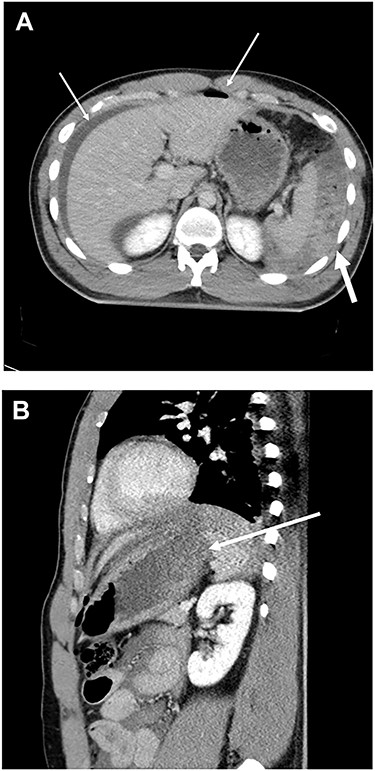

Our case was a 22-year-old man measuring 180 cm in height and weighing 86 kg. Two hours after eating a large amount of food, he was involved in a collision between his motorcycle and a motor vehicle. At the examination, he was alert and his vital signs were stable. The patient presented with an open skull fracture on the left forehead and described muscular defense throughout the abdomen. A whole-body computed tomography (CT) scan showed an open skull fracture reaching the left skull base (Fig. 1), and free air, ascites fluid, disruption of the gastric wall and a large amount of food residue behind the spleen (Fig. 2 and b). The head wound was first treated, and then, a laparotomy was performed on suspicion of a traumatic gastric rupture.

(A) CT scan of abdomen showed free air, ascites (thin arrow) and a large amount of food residue behind the spleen (thick arrow). (B) CT scan of abdomen showed disruption of gastric wall (arrow).